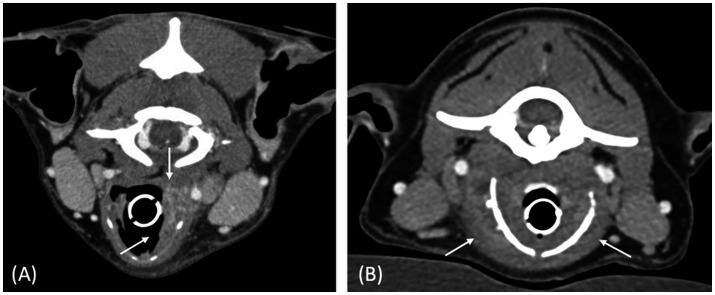

Results: Four dogs had laboratory reports compatible with a malignant neoplasia and three with an inflammatory process. The shape of the mass was defined as "ovoid" in all neoplastic masses and as "thickening" in cases of inflammatory processes. Masses were of various sizes (median length: 42 mm, range: 26-82 mm) and either unilateral (1/4 and 2/3 of neoplastic and inflammatory masses respectively) or bilateral. They were described as mineralized (1/4 and 1/3) and as having either an internal (1/4), external (2/4) growth pattern or both (1/4, 3/3). All masses had ill-defined margins and showed heterogeneous contrast enhancement. Two neoplastic and two inflammatory masses had a cavitary aspect. All but one case were associated with regional lymphadenopathy. Thyroid cartilage destruction was observed with two neoplastic and two inflammatory masses.

Clinical relevance: This case series describes CT features of laryngeal masses. The shape of the laryngeal mass may assist in determining its nature, inflammatory process was defined as "thickening" of the larynx and neoplasia as "ovoid"-shaped, whereas other studied features were inconsistently observed in both neoplastic and inflammatory conditions.